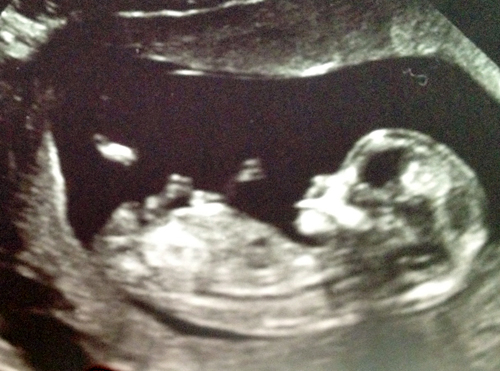

We had our NT scan yesterday at 12w2d! Baby measured 12w4d and the tech offered to tell the gender. Neither her nor I hesitated when we saw the nub. I really don't think this can turn into a penis at this point. Please let me know what you think. This was the *best* picture I got that was printed out. Of course, when we were inspecting the nub during the scan it was much more clear. Hopefully you all can see the nub as well in this picture. So definitely girl???